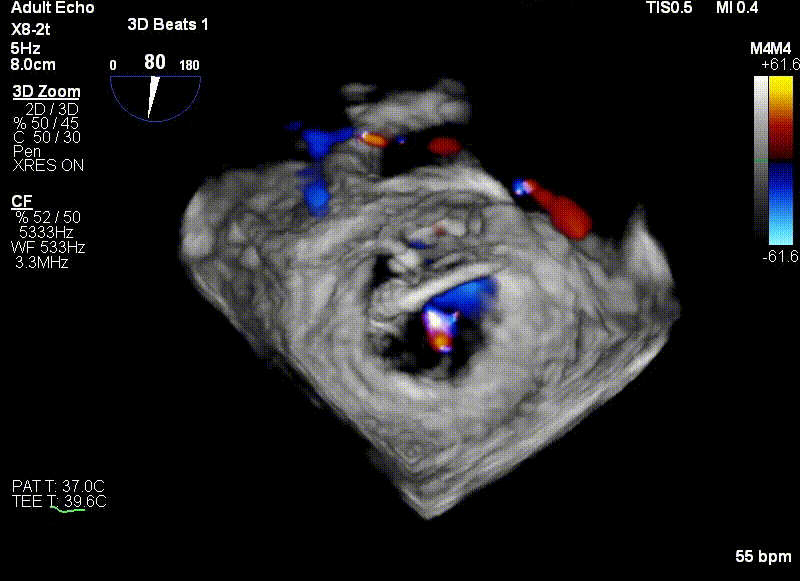

王建安教授调整二尖瓣夹轨迹和方向,使其轨迹垂直于二尖瓣环平面且指向心尖,定位于二尖瓣C1区且指向1-7点钟方位。

经食道超声引导后,王建安教授将二尖瓣夹NTR夹取C1区瓣叶,准确成功捕获C1前叶和后叶反流最严重区域,并予夹合。使二尖瓣在收缩期由大的单孔变成一大一小的双孔,显著减少了二尖瓣反流。